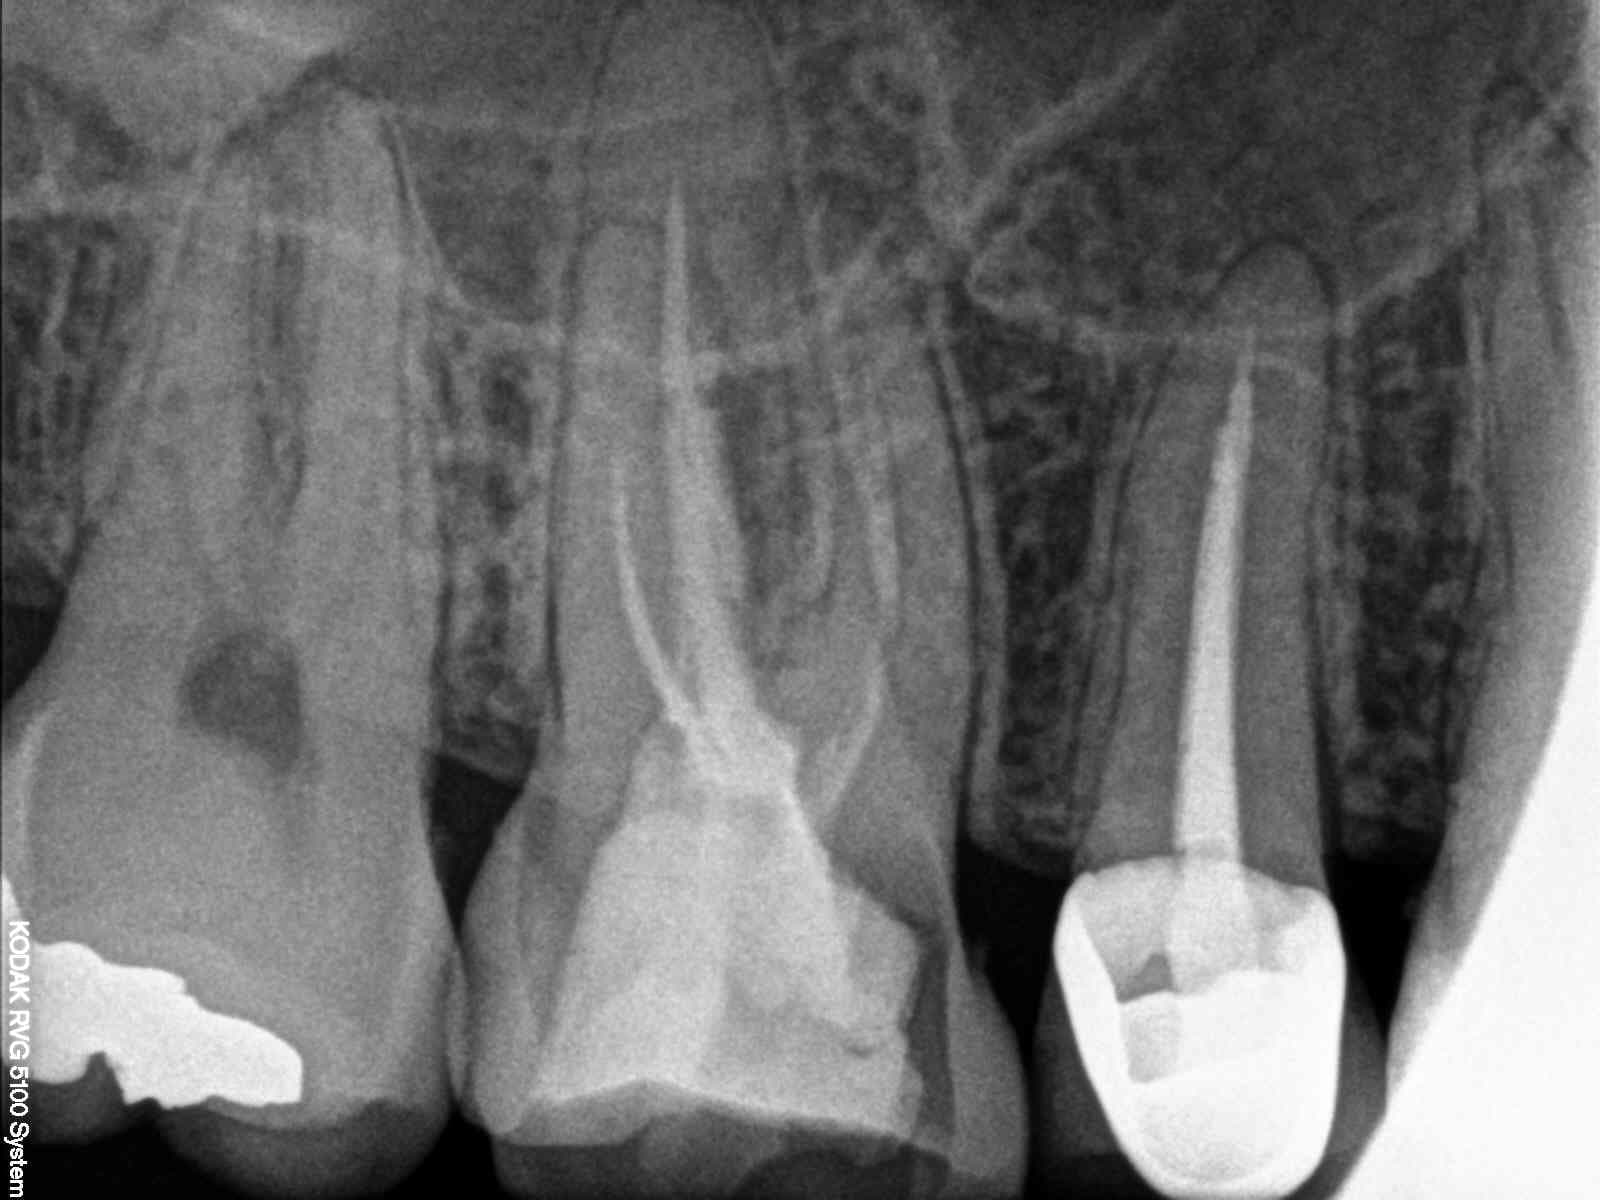

> Franchement un tel soin ne mérite même pas 20 euros. Alors arrêter pour certains

> de jouer les pleureuses. Tant que certains dentistes travaillerons de la sorte

> les gouvernants auront du grain à moudre. Et n'allez pas me dire que l'endo ne

> vaut rien donc on bâcle. Comment le dentiste peut justifier son prix de prothèse

> (IC et couronne) avec une telle "merde" en endo. Franchement même avec le

> plafonnement il prendrait encore trop cher. C'est cela qui nous fait mal.

Pas d'accord l'endo vaut son prix ( sur le cas en photo) et la prothèse aussi. On serait beaucoup plus cher en prothèse si on rattrapait. -)